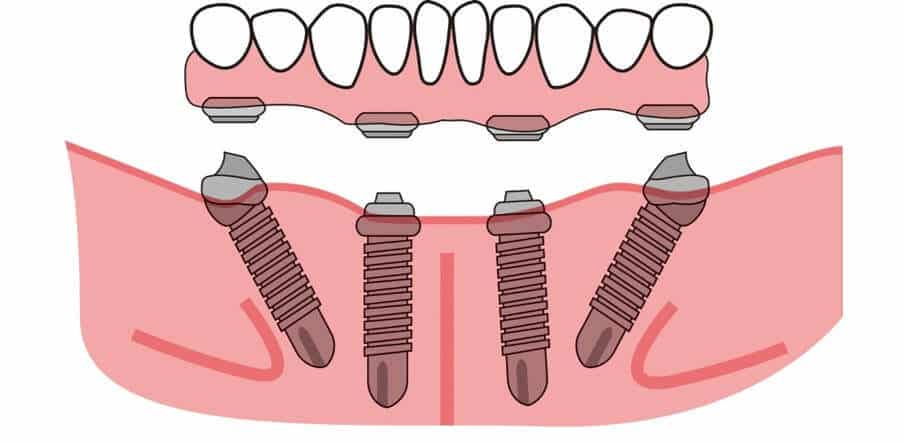

במידה ועצם הלסת חזקה ועבה רופא השיניים יכול לבצע all on 4, כלומר מיקום של 4 שתלים דנטליים שמקובעים לעצם הלסת ועליהם מורכב גשר שמחזיק את מערכת השיניים החדשה.